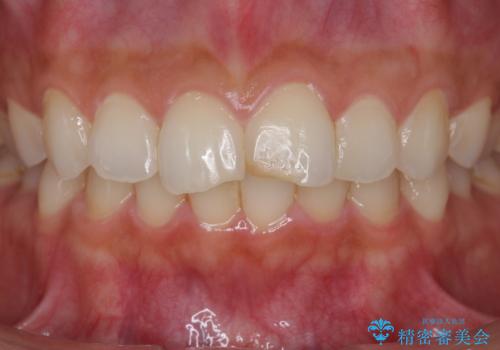

すり減った前歯の形態回復

- すり減ってしまった前歯の審美性の回復を希望され来院されました。

何度かレジン修復を試みたものの、脱離しやすく変色も気になる、とのことでセラミッククラウンによる審美性の回復を計画します。

右側は、クラウンにせず可及的に形態を整えることのみでの対応としました。

自然な色調のセラミッククラウンで審美性を回復することができ、大変満足いただけました。